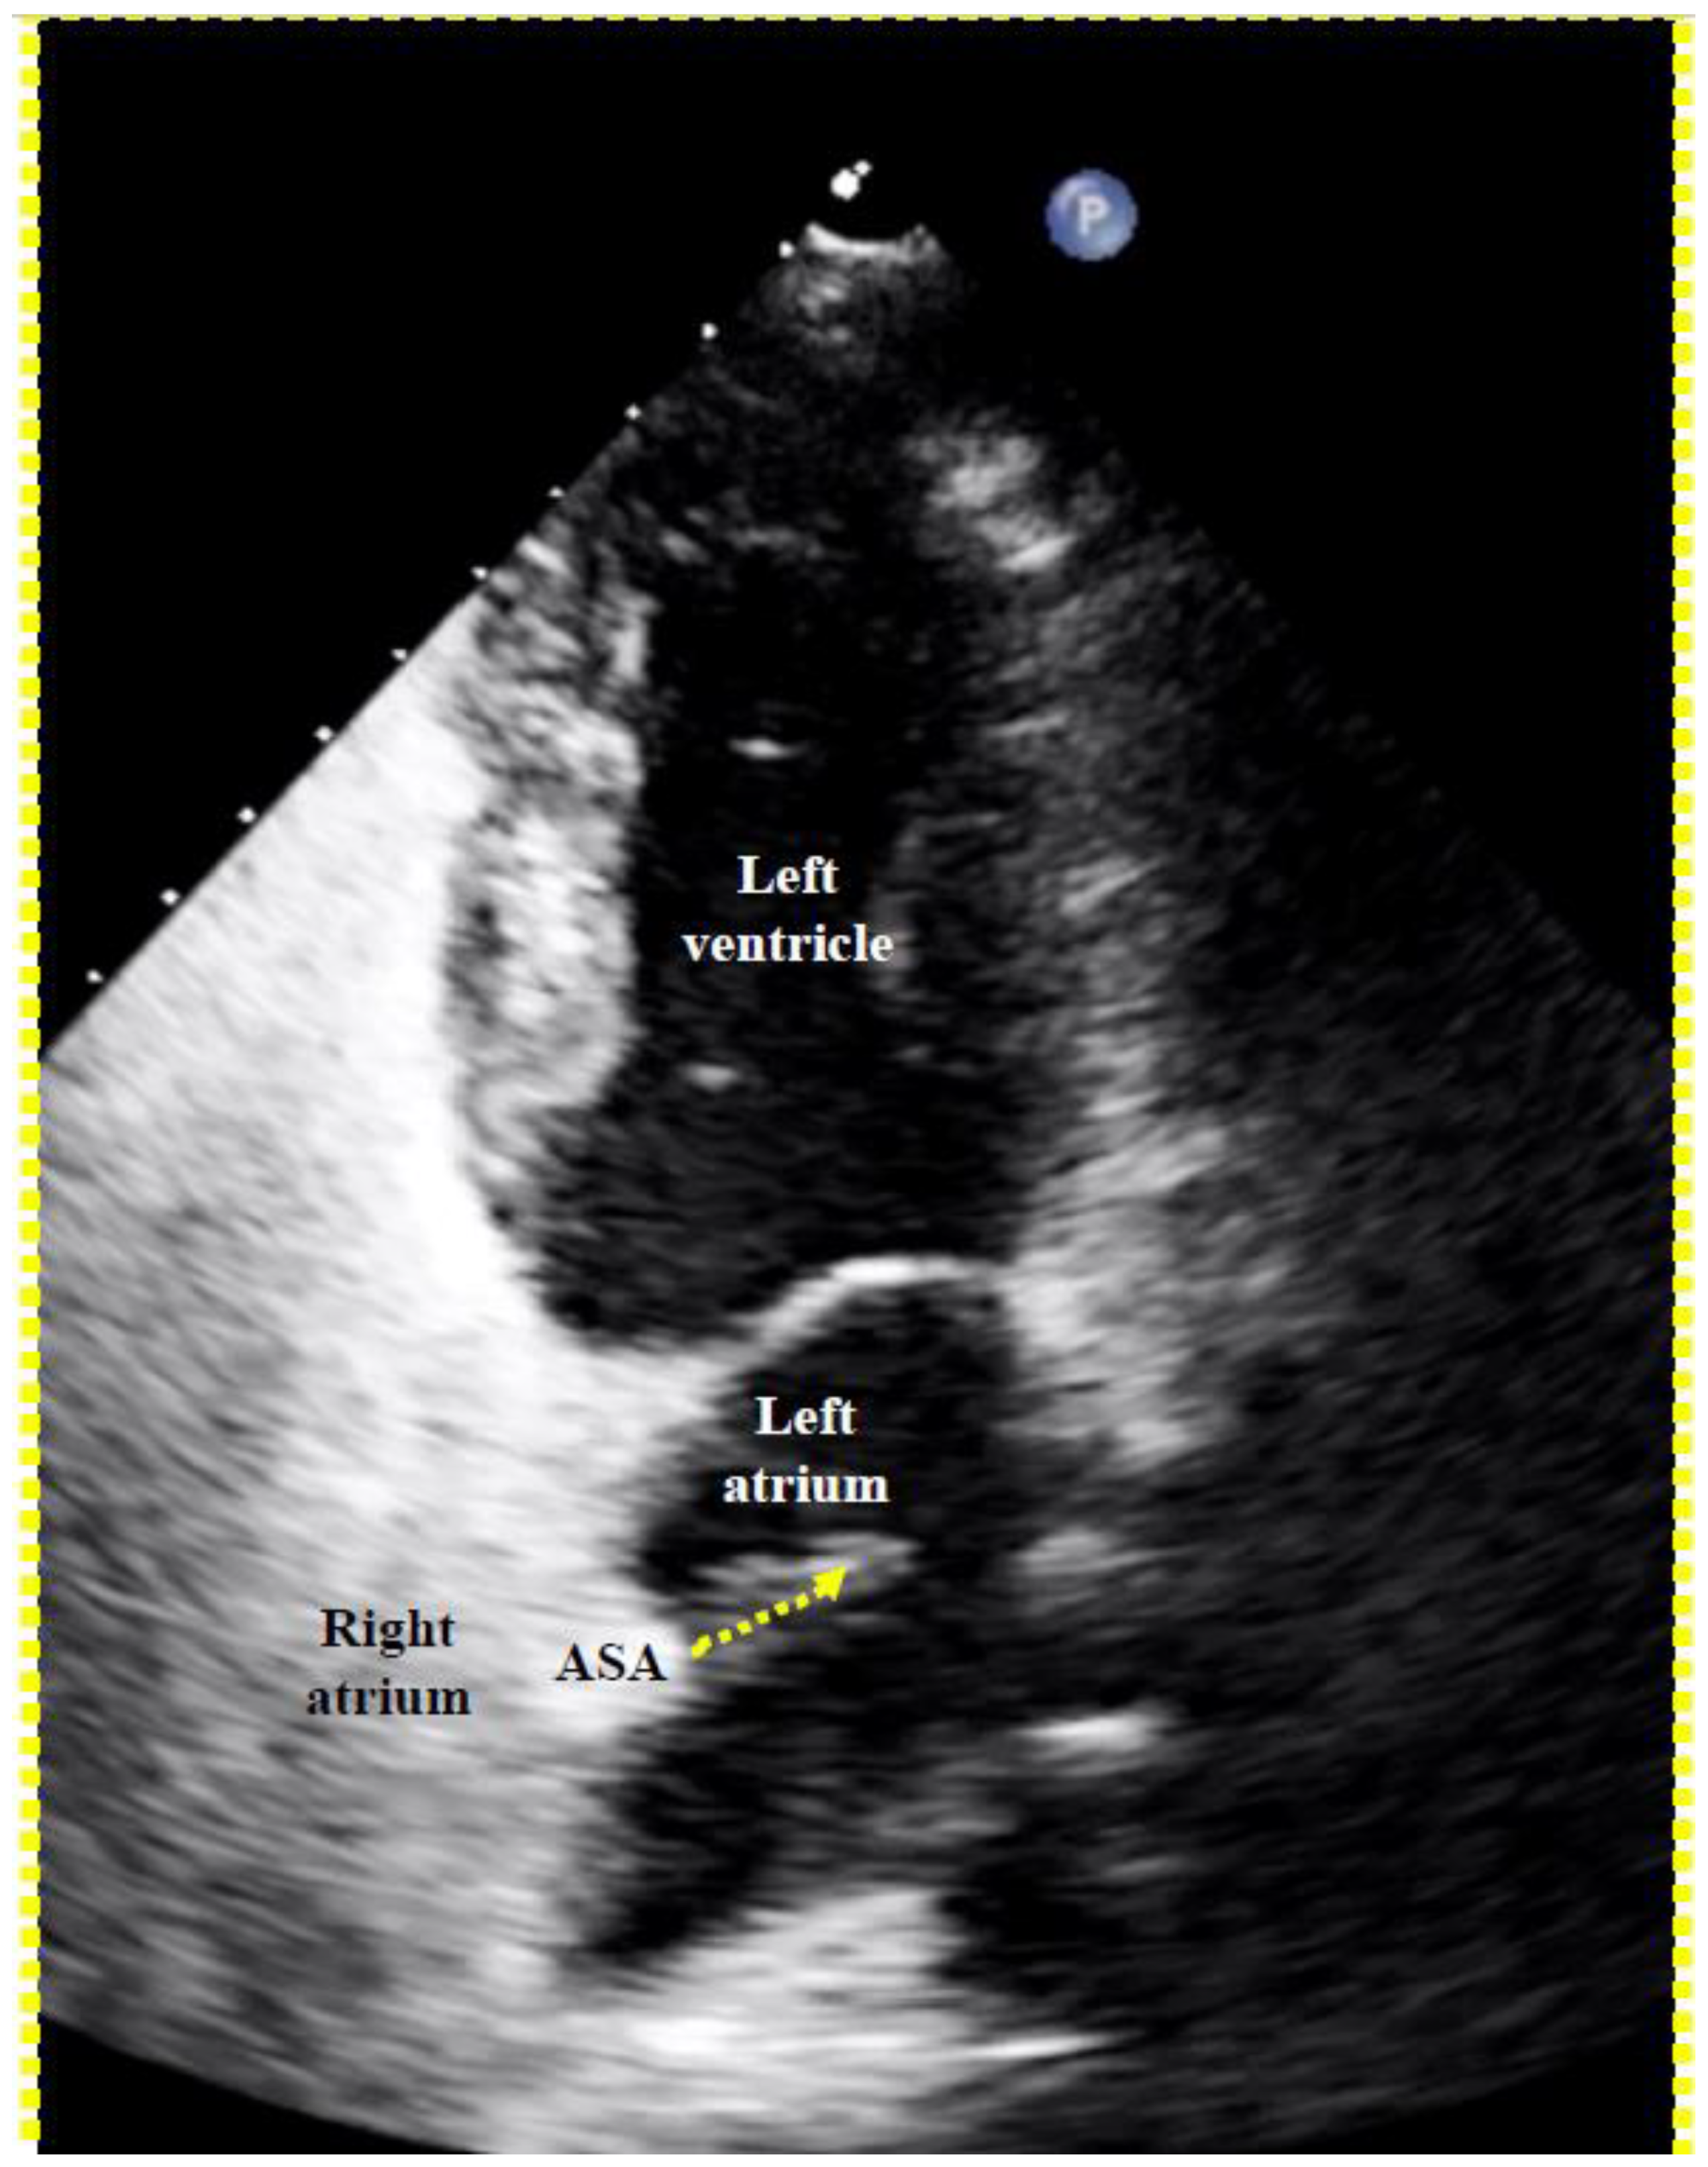

To screen for dangerous PFOs, i.e., large ones or those associated with an ASA [8], a Eustachian valve [9,10,11,12], or a Chiari network [13], a bubble test during a TTE suffices (Figure 5). The contrast liquid has to be injected at the end of a sustained Valsalva maneuver. A Valsalva maneuver, or pressing into the upper belly by a medical person during TEE if a sedated patient cannot perform a Valsalva maneuver, blocks the backflow of the venous blood into the thorax. Both atria become volume-depleted within 10 to 20 s. Upon Valsalva or pressing release, the venous blood gushes into the right atrium first, thereby pushing the PFO open towards the still underfilled left atrium.

Figure 5.

Proof of a patent foramen ovale (PFO) with right-to-left shunt with transthoracic echocardiography. A right-to-left bubble shunt (dotted arrow) is demonstrated with its origin in the region of a conspicuous atrial septal aneurysm (ASA).